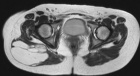

50 year old female presents with c/o enlarging mass in L buttock region. Hx of having had a mass excised from this same area five years earlier.

Zoom image: Radiological image Radiological image.